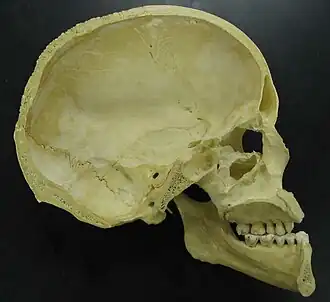

O crânio humano pode ser dividido em duas partes: o neurocrânio, que forma uma caixa protetora do cérebro, e o esqueleto facial ou esplancnocrânio.[2] O neurocrânio corresponde à parte superior e posterior do crânio que apoia as estruturas da face e protege o cérebro. É constituído principalmente por ossos e placas de cartilagem achatadas, formando uma cavidade onde ficam alojados o cérebro e vários órgãos dos sentidos - a visão, o olfato e o ouvido. Do neurocrânio fazem parte a calota craniana (ou calvária) e a base do crânio.[3]

A caixa craniana é formada pelos seguintes ossos: